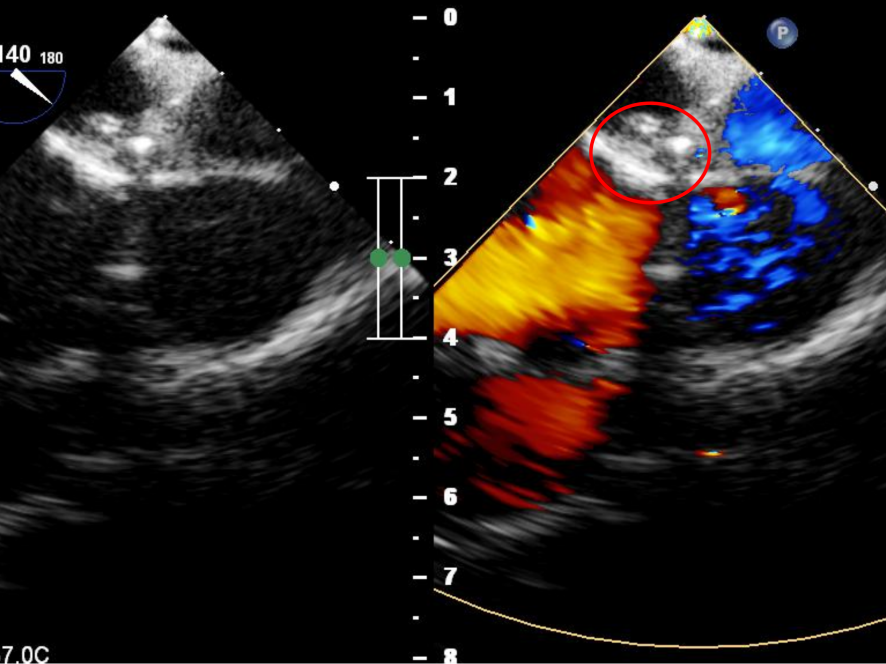

患者一为年轻男性,心脏超声显示:右心增大,室间隔及左室壁各节段厚度正常,收缩幅度正常。房间隔中部回声脱失约十余个毫米,缺损紧邻主动脉后壁。患者经心脏超声诊断为先天性心脏病房间隔缺损,房水平左向右分流。

患者二为年轻女性,入院心脏超声显示:右心轻大,左心内径正常;房间隔发育菲薄,中部回声脱失约十余个毫米,缺损距主动脉侧3mm;室间隔延续完整。经心脏超声诊断为先天性心脏病房间隔缺损,房水平左向右分流。

两例手术均在单纯超声引导下,行经皮ASD介入封堵,患者局部麻醉,全程意识清醒。于其右腿股静脉穿刺,置入导管导丝,并测量工作距离,建立顺畅轨道。结合术前评估情况, 术中超声引导下,手术团队均沿16F鞘管将大小合适的可降解封堵器精准送至房间隔缺损处,并遵循一贴、二扣、三锁、四剪、五撤的“5S”操作法及“轻”推“慢”锁步骤释放封堵器。超声观察封堵器双盘先后展开,轻拉、轻推钢缆及鞘管使其成型并紧密贴靠房间隔上,牵拉测试封堵器稳定性,超声确认无残余分流、无瓣膜关闭不全,封堵器形态、位置良好后,锁定并彻底释放封堵器,剪断抽出成型线,复查超声,无残余分流,封堵完全,撤出钢缆,两例手术均取得圆满成功。